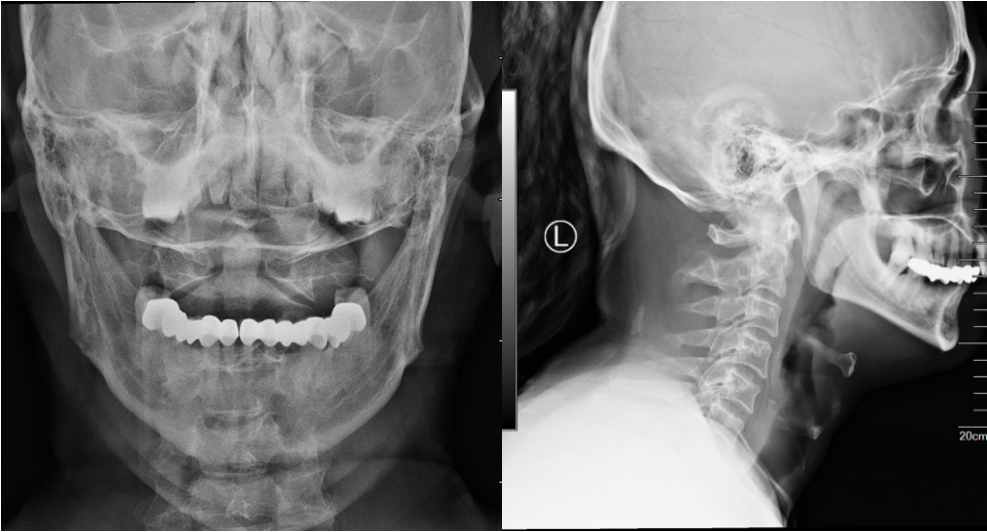

CT图像清晰显示患者C2齿状突骨折,并有移位